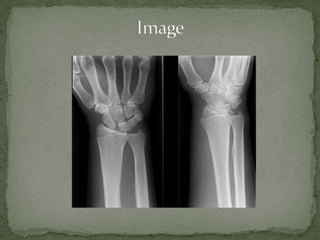

A 45-year-old male presents to the emergency department with right wrist pain after falling on an outstretched hand while working in his yard. On examination, his right wrist is tender over the distal radius with no other deformities or neurological deficits. A chauffeur's fracture is suspected due to the mechanism of injury, which is an avulsion fracture of the radial styloid that often requires surgical fixation. Close orthopedic follow up is needed to properly evaluate and treat the injury.